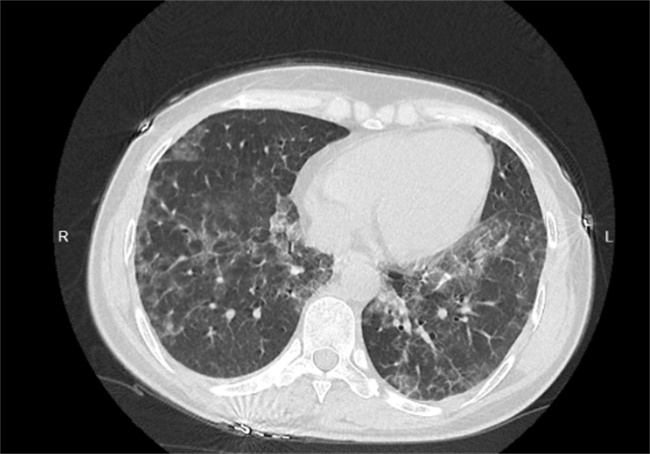

白肺是指肺部组织会呈现出大片的白色病变现象。主要是进行胸部X线片检查,还有胸部CT检查时出现一些不同的白色病变。白肺的表现一般都是出现在重症肺炎上,可能是细菌病毒又或者是其他危害,生物感染之后,没有得到控制所导致。除了和新冠肺炎有关之外,和下面的这些因素也有关系。